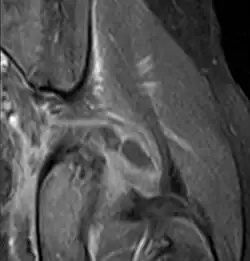

Coronal fat suppressed post contrast image showing a multiloculated bacterial abscess in the left gluteus minimus muscle due to tropical pyomyositis.